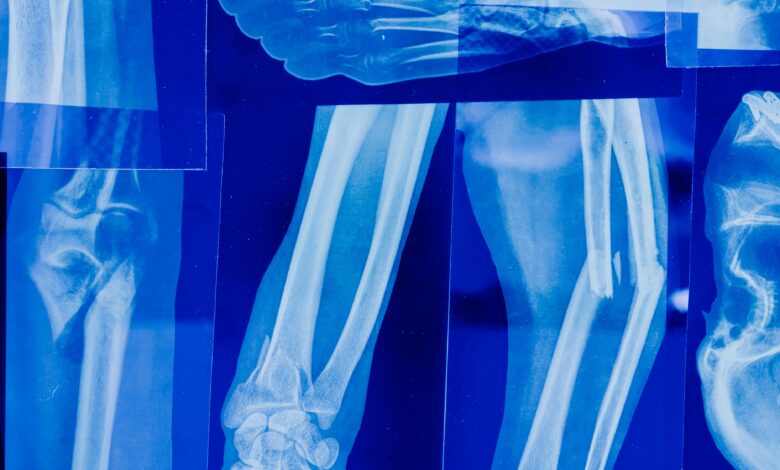

🩻 الأشعة السينية (X-Ray): أداة أساسية للتشخيص الطبي

الأشعة السينية (X-Ray) هي فحص تصويري سريع يستخدم الأشعة لتكوين صور للعظام والأعضاء الداخلية، مما يساعد الأطباء على تشخيص الإصابات والأمراض بدقة وسرعة.

🩺 استخدامات الأشعة السينية

- تشخيص الكسور والإصابات العظمية:

تحديد مكان وكثافة الكسور وتشخيص مشاكل المفاصل. - أمراض الرئة والجهاز التنفسي: